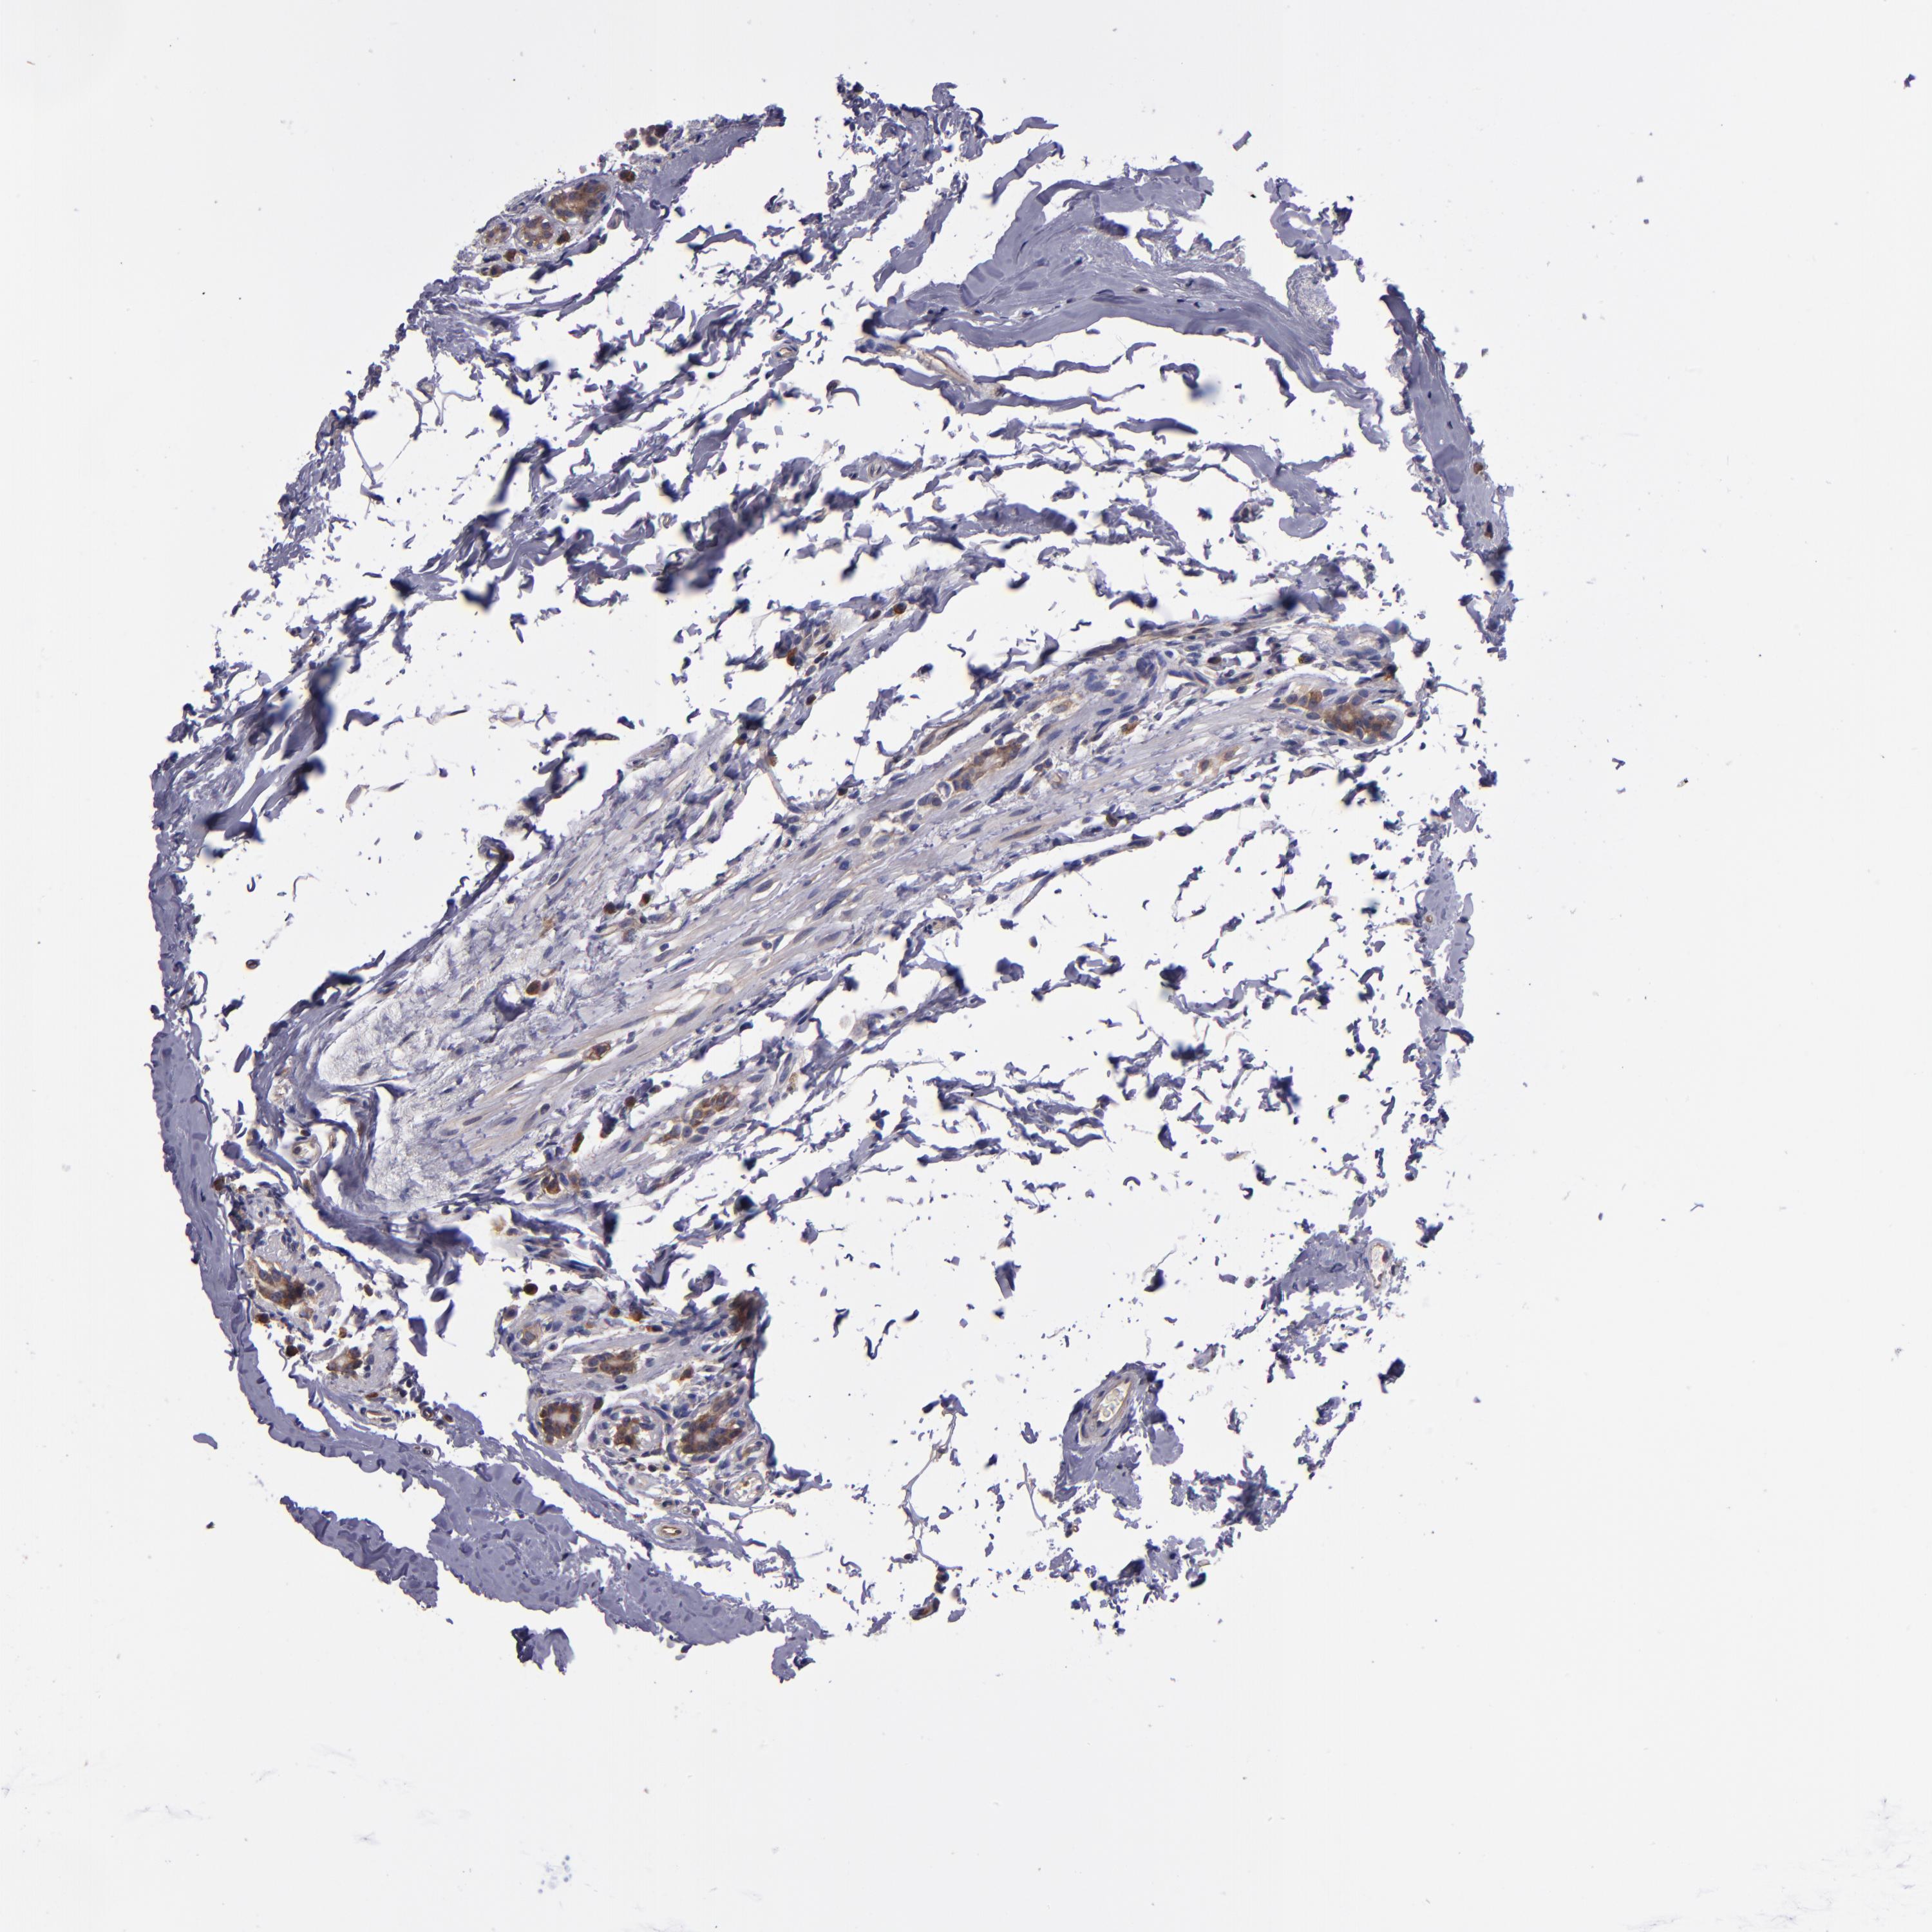

CANCER BREAST CANCER Show tissue menu

BRCA TCGA BRCA VALIDATION PROTEIN EXPRESSION